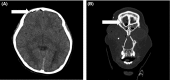

Case: We report a case of post-traumatic hypopituitarism in a 9-year-old boy who was injured in a car accident.

Outcome: Post-traumatic hypopituitarism might be caused by moderate to severe head trauma, and while this possibility has recently drawn attention in adults, few reports are available regarding children. Our patient experienced head and facial injury, resulting in post-traumatic hypopituitarism. Six hours after injury he suffered from diabetes insipidus and hormone replacement therapy was started. On day 12 he underwent facial fracture reduction under general anesthesia. On day 24 he was discharged from the hospital. One year after the injury, secretory function and water dehydration tests suggested the possibility of post-traumatic hypopituitarism.